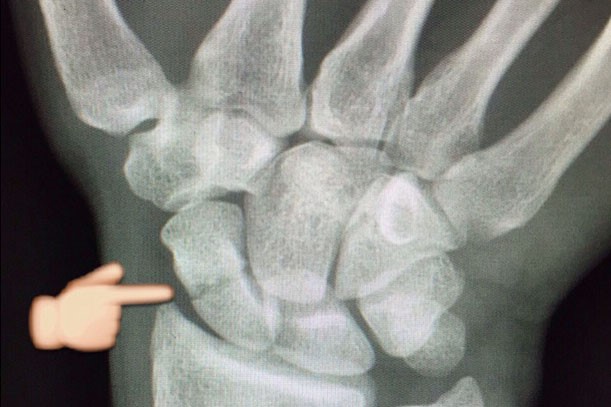

Штефан Брадль неудачно упал во время гонки MotoGP Гран-При Нидерландов и сломал ладьевидную кость. Немецкого гонщика успешно прооперировали в родном городе Аугсбурге.

Доктор Штефан Кришак вставил винт, чтобы зафиксировать перелом и ускорить процесс восстановления. Операция прошла успешно, и вскоре Брадль снова сможет вновь сесть в седло своего мотоцикла.